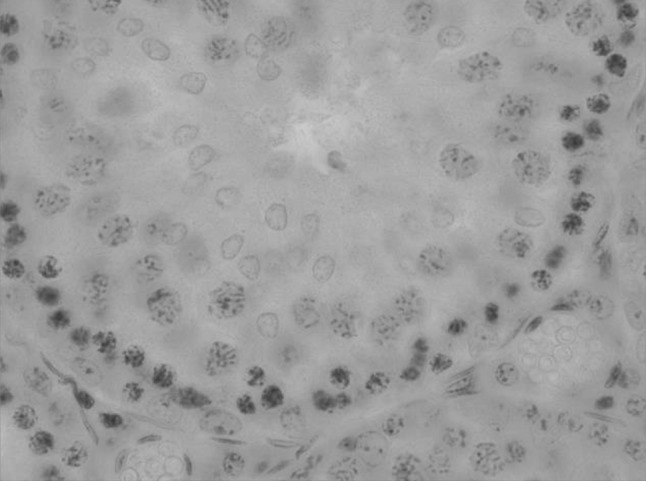

We have also carried out testis tissue histological examination of the animals affected by bichrome acute exposure. Cytological profile of the convoluted tubules’ spermatogenesis is represented in the Figs. 1, 2, 3, 4, 5, 6.

Testis convoluted tubules cross-section in preleptotene stage. H&E ×1000

Testis convoluted tubules cross-section in preleptotene and leptotene stage. H&E ×1000

Testis convoluted tubules cross-section in leptotene and zygotene stage. H&E ×1000

Testis convoluted tubules cross-section in zygotene stage. H&E ×1000

Testis convoluted tubules cross-section in pachytene stage. H&E ×1000

Testis convoluted tubules cross-section in diplotene and diakinesis stage. H&E ×1000

We have been also identifying prophase stages of the reduction division in the rats of the experimental and control group (Table 2). Comparison of the convoluted tubules’ average diameter of the control animals and the experimental group, showed diameter and lumen increase of the seminiferous tubules in the bichrome-exposed animals. Thus, convoluted tubules’ average diameter of the control animals was 263.72 ± 2.37 µm, convoluted tubules’ diameter of the experimental animals increased 10 % more, being 291.15 ± 3.11 µm. At that, sharp decrease of the spermatogenesis coefficient took place, which decreased by 68 %; also considerable increase of the number of tubules with “plugs” took place.